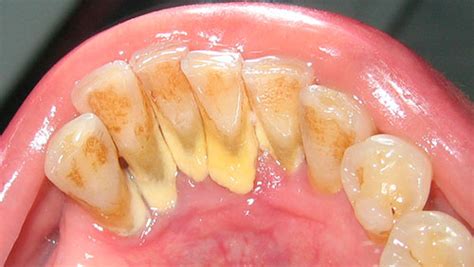

El sarro, también conocido como cálculo dental o tártaro, es un problema bucodental muy común que afecta a gran parte de la población. Consiste en la calcificación de la placa bacteriana, transformándose en una placa dura que solo puede ser retirada por un especialista en odontología.

De hecho, el sarro duro detrás de los dientes afecta a más del 70% de los adultos, convirtiéndose en una de las principales causas de enfermedades periodontales. Este problema, aparentemente invisible pero con consecuencias significativas para la salud bucodental, requiere un enfoque profesional y especializado para su correcta eliminación.

- Coloración del sarro: El sarro duro detrás de los dientes presenta inicialmente una coloración amarillenta que puede evolucionar hacia tonos marrones o incluso negros, dependiendo de factores como el tabaquismo, el consumo de té, café o ciertos alimentos.